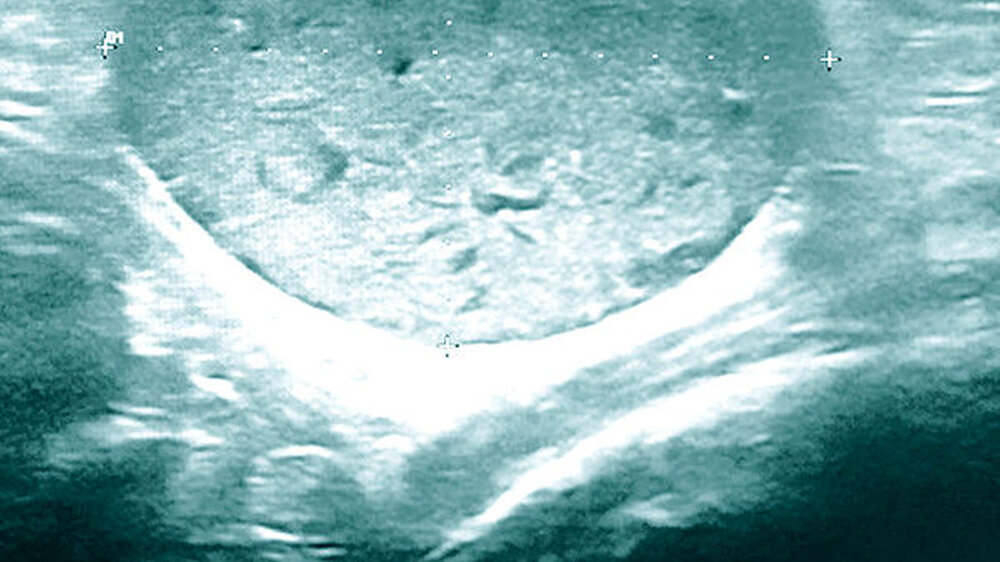

Als weiterführendes bildgebendes Verfahren wurde zunächst die Sonografie gewählt. Hier zeigte sich ein strukturierter, inhomogener Befund mit hyper- und hypoechogenen Bereichen und einer dorsalen Schallverstärkung. In direkter räumlicher Nähe der Raumforderung war eine Arterie sonografisch erkennbar und eine räumliche Beziehung zu einem Ast des Nervus facialis nicht auszuschließen (Abbildung 1).